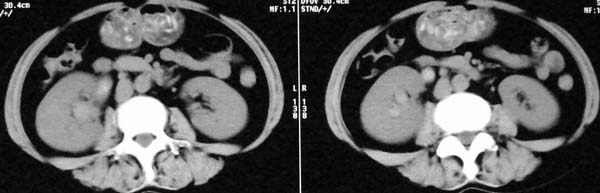

以下是引用dr.yang在2008-11-9 21:56:00的发言:[br]右肾上极占位?建议增强

以下是引用x-man在2008-11-9 22:30:00的发言:[br]建议先增强,右肾影明显增大,上极见边不清低密度肿块影,肿瘤待定.

以下是引用卜一在2008-11-10 8:09:00的发言:[br]建议先增强,右肾影明显增大,上极见边不清低密度肿块影,肿瘤待定.支持!另:第一次碎石是否肾受到损伤?合并感染?不知第一次碎石前是否做过彩超?

以下是引用dsl555在2008-11-9 23:57:00的发言:[br]建议先增强,右肾影明显增大,上极见边不清低密度肿块影,肿瘤待定. [br] [br]